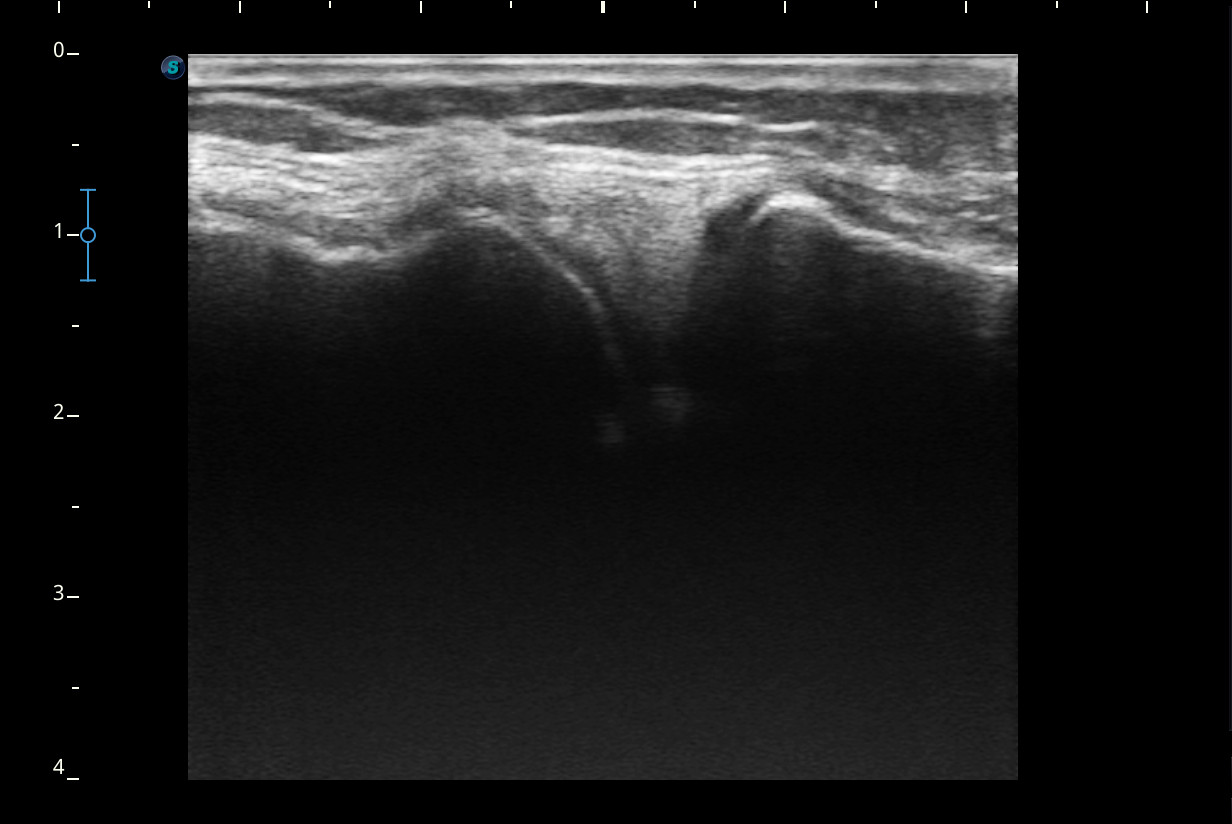

Se realiza ecografía de rodilla.

Descripción de los hallazgos ecográficos y las imágenes más relevantes para la resolución del caso

Rodilla sin derrame articular. No se aprecian lesiones en Ligamentos colaterales. Ligamento rotuliano sin hallazgos valorables. Rotura menisco interno y dudosa fisura menisco externo. Tendones rotuliano y cuadricipital normales.

Resonancia magnética confirma rotura cuerno posterior menisco interno.